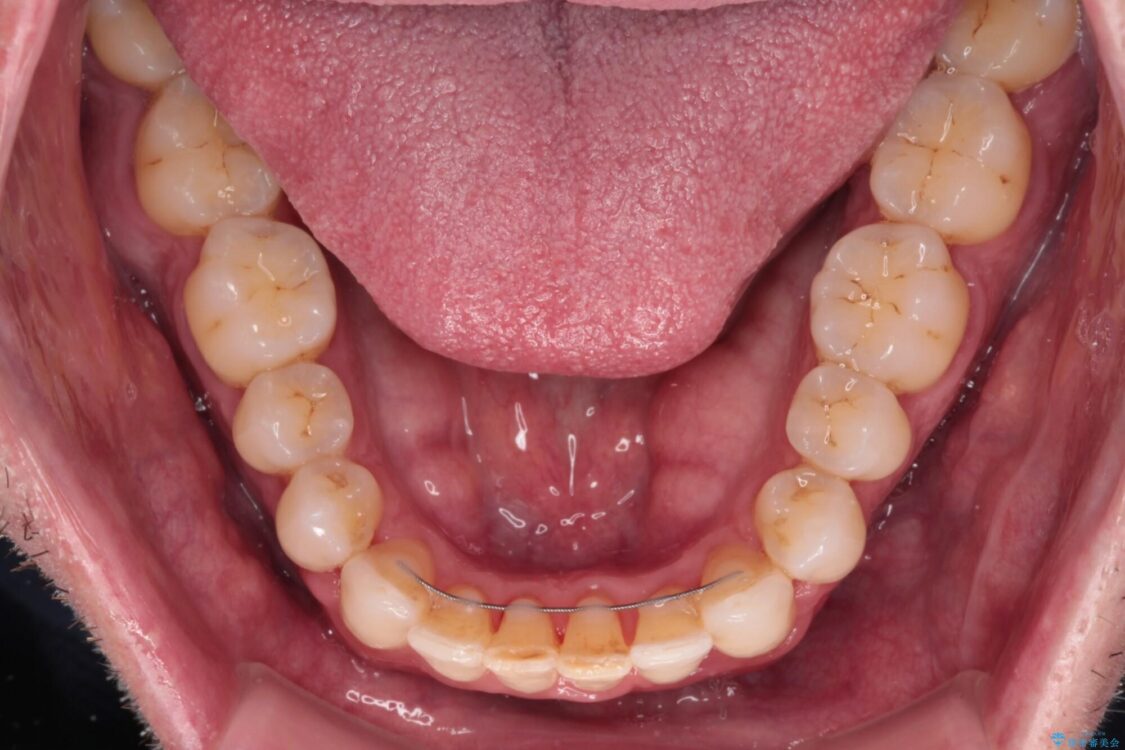

治療後

• 前歯でものを噛みきりたい 目立たない装置でのワイヤー矯正 治療後画像